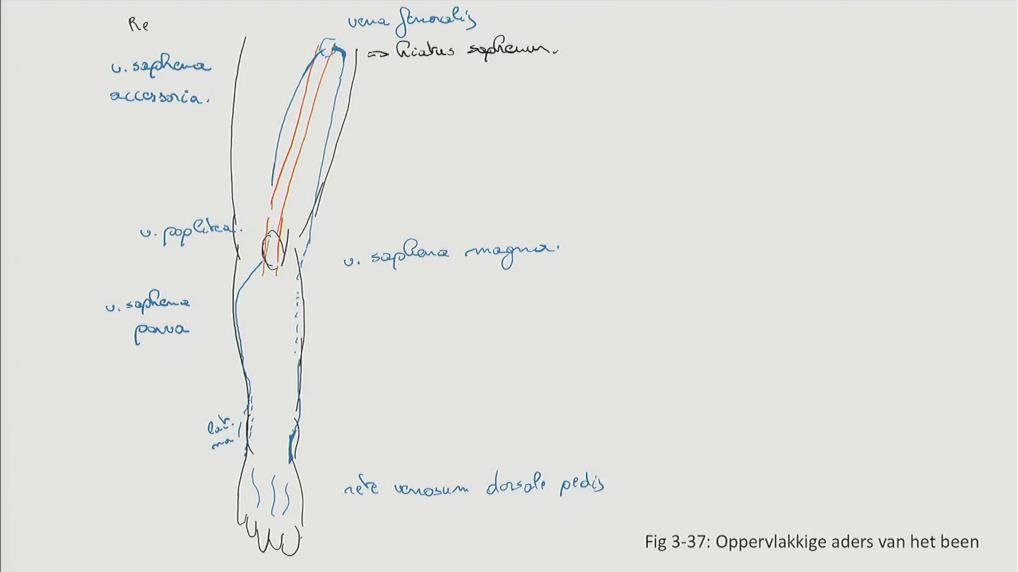

Fig 3.37: Oppervlakkige aders van het been

-

diepe bloedvaten

malleolus lateralis malleolus medialis rete venosum dorsale pedis -

v saphena magna (voor malleolus medialis, via hiatus saphenus naar v. femoralis)

v saphena parva (achter malleolus lateralis, tussen koppen m. gastrocnemius, naar v. poplitea in fossa poplitea) v saphena accessoria (via hiatus saphenus naar v saphena magna)